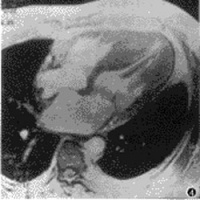

近些年来人们对血管内皮的研究发现,在冠心病患者中血管内皮产生和释放的内源性血管舒张因子一氧化氮(NO)及前列腺素(PGI2)减少,而强有力的缩血管物质内皮素及血管紧张素Ⅱ的分泌增多。内皮素和血管紧张素Ⅱ除了血管作用以外,还具有促进心肌细胞肥大、间质纤维化和引起胎儿型收缩蛋白基因表达的作用,直接参与了心力衰竭的病理生理过程。这种内皮功能的失调,可以刺激血管的收缩,平滑肌增殖及血管壁的脂质沉着并可能促使冠状动脉内血栓形成,使心肌缺血导致左室功能受损。可见内皮功能失调也是导致心肌缺血和心力衰竭的重要机制之一。晚近,TREND(Trial on Reversing Endothelial Dysfunction)已证明,血管紧张素转换酶抑制剂可以逆转或改善血管内皮功能失调。而且这一血管假说,也已为4S(Scandinavian Simvastatin Survival Study)及CARE(Cholesterol and Recurrent Event)试验所证实,并为心力衰竭的治疗提供了部分理论基础。病理:ICM病人心脏增大重量可达450~830g。心脏扩大,以左心室腔扩大为主如双心室腔均严重扩大,心脏外观可呈球形。心室壁由于代偿性肥厚和局部纤维化或瘢痕形成而厚薄不均,与正常人相比,ICM病人的心室壁较薄并且心室壁厚度与增大的心脏不成比例。冠状动脉常有弥漫而严重的粥样硬化,导致冠状动脉管腔狭窄和血栓形成,常有多支冠状动脉病变组织学检查常见有心肌细胞变性、坏死和纤维瘢痕形成心室壁常见大片瘢痕组织。有近半数的病人心室内可见附壁血栓。镜下观察,心肌线粒体内膜破坏嵴减少。线粒体呼吸链相关酶活性下降心肌纤维可见I带增宽,严重缺血时可见痉挛带形成。